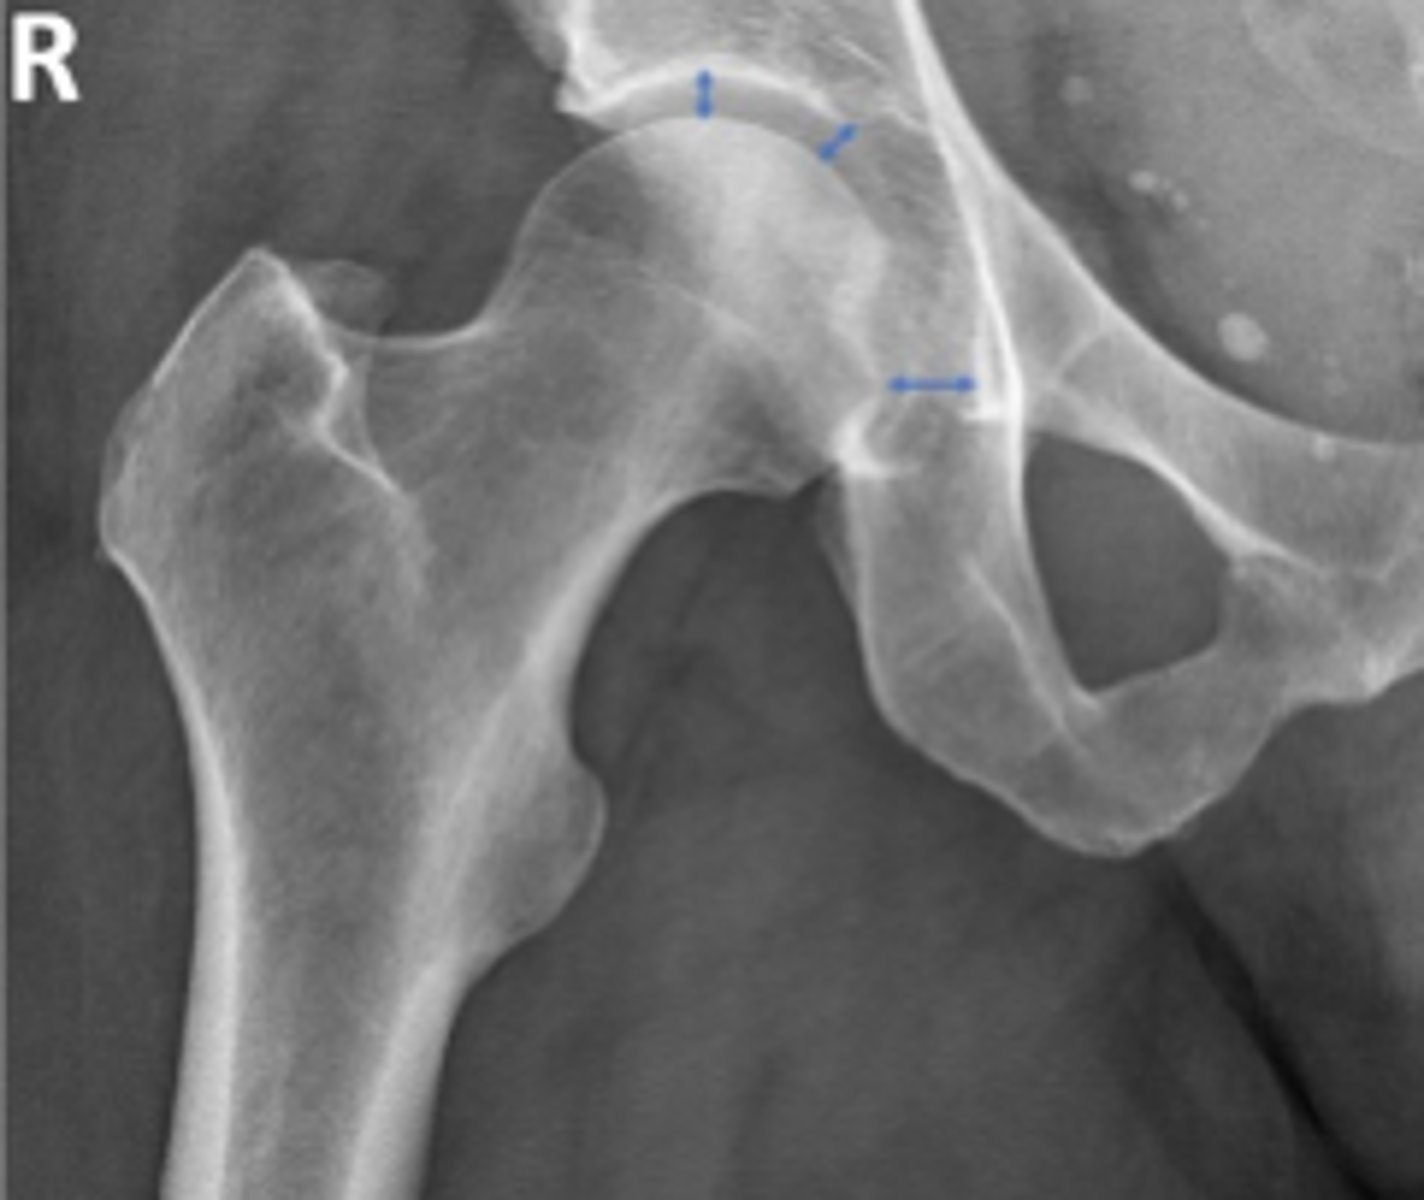

Right AP hip

What is the name of the radiographic view?

Right frog-leg hip

Posterior rim of the right acetabulum

What are the arrows pointing to?

Anterior rim of the right acetabulum

Lesser trochanter of the right femur

Greater trochanter of the right femur

Intertrochanteric line of the right femur

Right ischial tuberosity